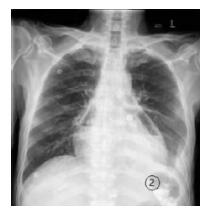

入院后复查心电图(2016年3月31日11:30)示:窦性心动过速,Ⅱ、Ⅲ、aVF 、V4-V6导联ST段抬高(图 1A)。肌酸激酶同工酶(CK-MB)和心肌肌钙蛋白(cTnI)在正常范围;血常规:白细胞总数19.9×109/L,中性粒细胞93.3%,血红蛋白124 g/L;C反应蛋白(CRP):165.5 mol/L;超声心动图(GE Vivid E9)检查示:肺气干扰,图像质量差。室壁运动无异常,少量心包积液。急诊胸部CT(图 1B)示:食管癌术后,心包积气,双侧胸腔积液,右上肺斑片影。上消化道碘油造影(图 1C)示:心包积气,食管癌术后,左侧胸腔胃,吻合口正常。入院诊断“心包积气,急性心包炎”,请胸外科、消化科等会诊后,给予CCU监护、吸氧、禁食,胃肠减压,全胃肠外营养,头孢哌酮舒巴坦静脉滴注等治疗,并抽取外周静脉血标本作血培养。4月1日患者诉说话、翻身或坐起时胸痛,平卧后胸痛可缓解。测体温正常,血压100/62 mmHg,复查CK-MB和cTnI均正常,降钙素原11.53 ng/mL。请感染科会诊后将抗生素改为亚胺培南西司他丁钠联合阿奇霉素抗感染治疗。4月3日复查全胸片(图 2)示:心包积气、积液(积气较2日前有所吸收),左侧少量胸腔积液。血常规:白细胞总数 9.7×109/L,中性粒细胞 80.1%,血红蛋白130 g/L;CRP 143.0 mol/L;降钙素原2.89 ng/mL。血电解质在正常范围。双侧血培养48 h(需氧和厌氧菌)均无细菌生长。继续禁食、胃肠减压、胃肠外营养、抗生素等治疗。

图 2 患者全胸X线片结果